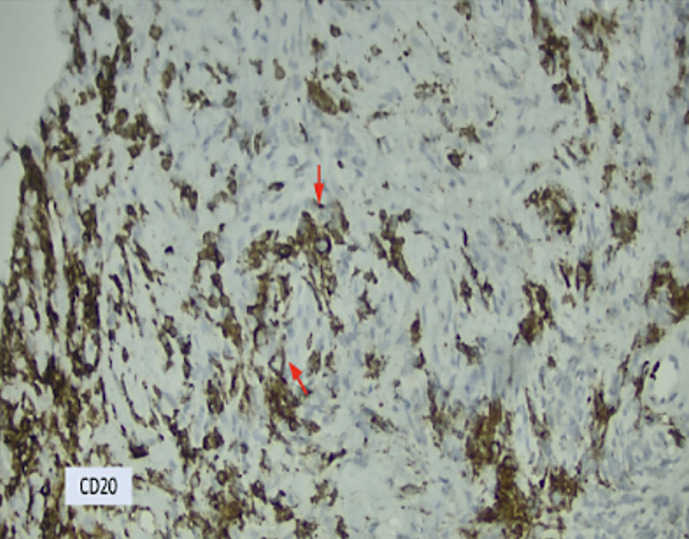

Case report: We present a rare case of PMBCL in a 39-year-old male with a bulky mediastinal mass that resulted in superior vena cava thrombosis and cardiac tamponade. Diagnostic discordance between histopathological and molecular data led to a delay in interception of this entity. Histopathology findings were suggestive of spindle-cell neoplasm. Contrastingly, next-generation sequencing (NGS) and immunohistochemistry (IHC) yielded a molecular diagnosis of PMBCL. IHC staining revealed that the atypical cells were positive for CD20, PAX5, CD79a, CD30, CD23, MUM1, and weakly positive for MAL (myelin and lymphocyte) protein. NGS showed increased expression of TNFRSF8 and CD274 genes, which encode CD30 and PDL1 proteins, respectively. The patient was successfully treated with the R-Hyper-CVAD protocol without consolidative radiotherapy.